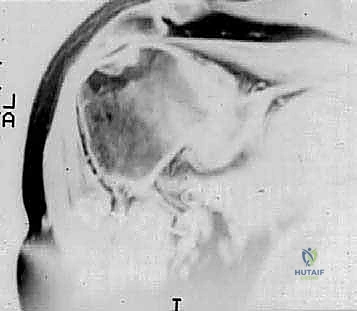

Radiographic findings in primary osteoarthritis include subchondral sclerosis and cyst formation, osteophyte formation, and asymmetrical posterior joint space narrowing ( FIG 4A,B ). 20

A B

A

B C

FIG 4 • Radiographic findings in osteoarthritis include osteophyte formation, especially on the inferior humerus as seen on the AP view ( A ), and asymmetrical posterior glenoid wear with posterior subluxation, as seen on the axillary view ( B ). C. CT scan reveals a large inferior humeral osteophyte and a type C glenoid, with increased glenoid retroversion. D. Coronal MR image in a patient with rheumatoid arthritis reveals an intact but very thin rotator cuff with erosion of the humeral attachment site, and evidence of rotator cuff dysfunction (ie, proximal humeral migration).

D

Computed tomographic (CT) scans are helpful in quantifying bone loss in patients with posterior subluxation ( FIG 4C ).

MRI is useful in patients with rheumatoid arthritis to determine rotator cuff integrity ( FIG 4D ).